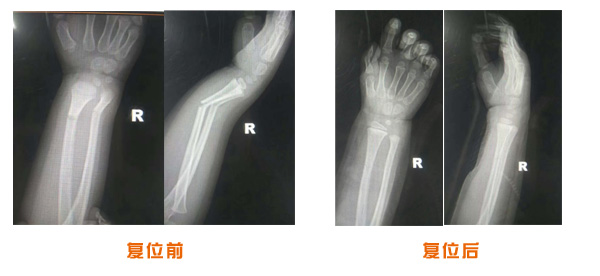

肥城市安駕莊梁氏骨科醫院是一所以梁氏手法正骨配合膏藥為特色的現代化??漆t院。

梁氏骨科術始創于清雍正年間,歷經八代,至今已有三百年歷史。據1929年泰安縣志載“梁瑞圖先生,字增生,號蓮峰,安駕莊人,精岐黃并發(fā)明接骨,凡跌打車凡跌打車軋皮不破而碎骨者......【詳細】 |